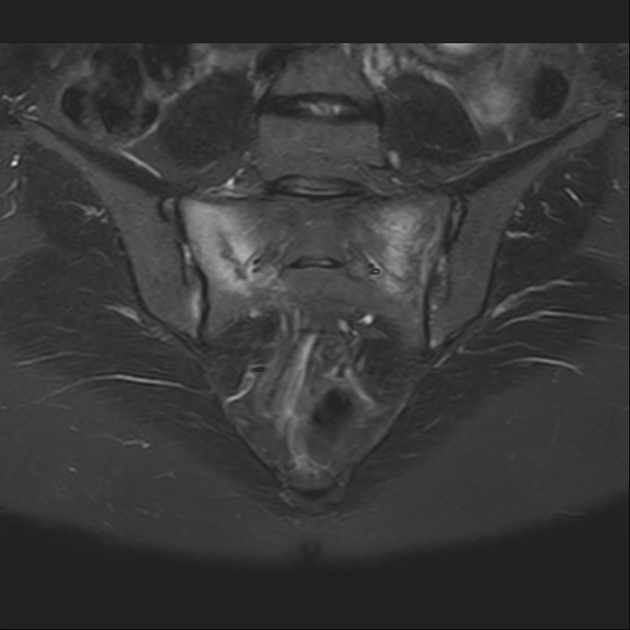

T2

磁共振影像表现